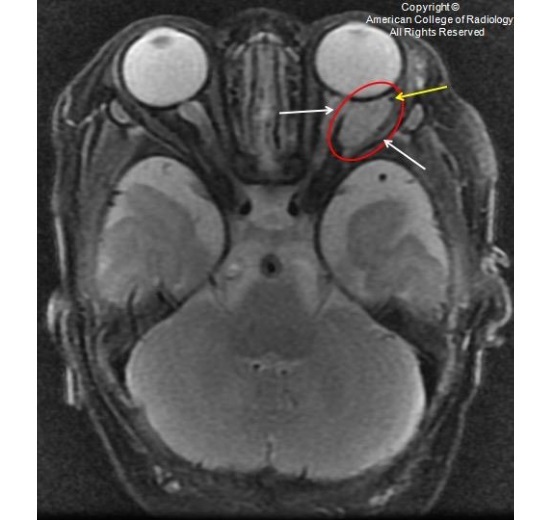

图 2 为 T2,眼眶内可见一均匀长 T2 信号(红圈),未侵及眶内肌肉和神经(白色箭头)。外前方可见一流空信号(黄色箭头)

图 3 为 T2,眼眶内可见一均匀长 T2 信号(红圈),未侵及眶内肌肉和神经(白色箭头)。外前方可见一流空信号(黄色箭头)